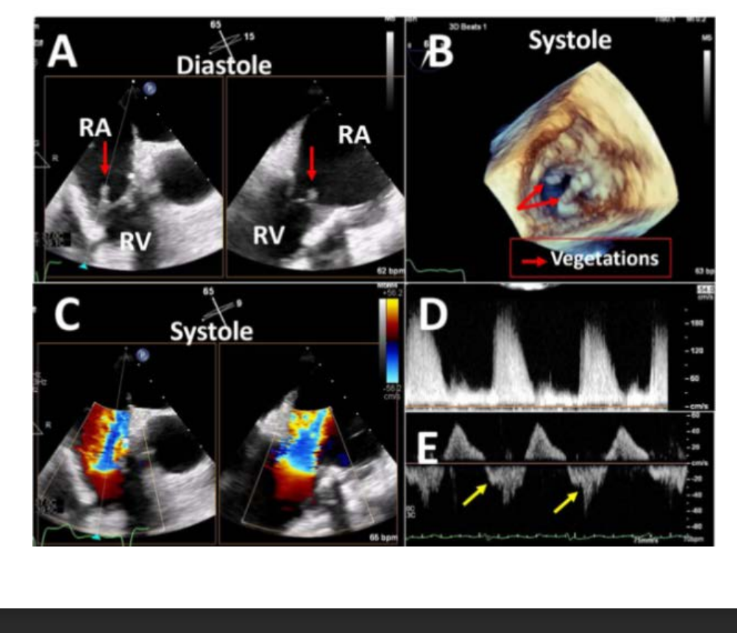

Causes of mitral prosthetic stenosis include: what 4 things

Degeneration

Thrombus

Pannus

Vegetations

2D demonstrates what two things of bioprosthetic leaflets or what of one or more mechanical?

what should also be suspected when there is a narrowed, and what velocity color Doppler TV inflow pattern?

2D demonstrates thickened and/or restricted motion of bioprosthetic leaflets or reduced excursion of one or more mechanical

Stenosis should also be suspected when there is anarrowed, aliased high-

Complications include: name 4

Thrombosis

Vegetation